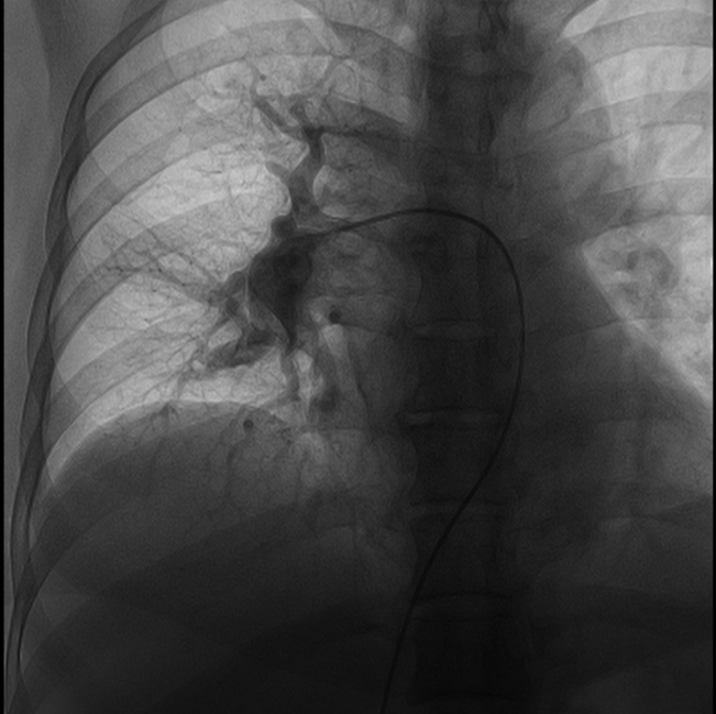

患者慕名至我院后,我科专家进一步对其进行了相关检查,最终诊断为:慢性血栓栓塞性肺动脉高压。心内科周亚峰副院长、陈弹主任、赵良平主任及团队成员进行深入讨论,并邀请呼吸科、血管外科与介入科等进行多学科(MDT)会诊,最终决定对其进行右心导管及肺动脉造影检查,结果提示肺动脉收缩压52mmHg,平均肺动脉压33mmHg,左右各肺动脉及其分支多发栓塞,可见多处血栓影及马赛克征。对右肺动脉A3、左肺动脉A1+2、左肺动脉A9行球囊扩张术,扩张后复查造影远端血流恢复良好。手术后患者的症状得到明显改善,心功能逐渐恢复,住院5天后平稳出院。出院后患者继续进行家庭氧疗、抗凝、利奥西呱降肺动脉压力等治疗,并密切随访中。随访至今,患者情况良好。